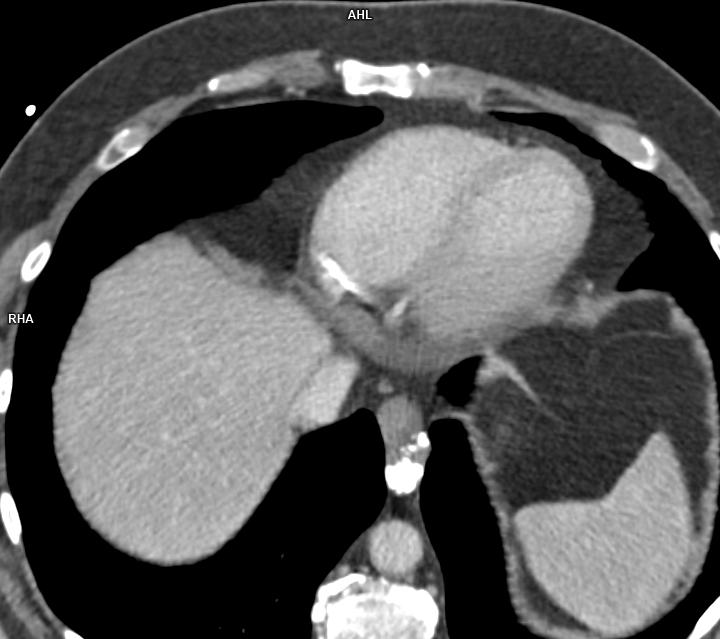

Figura 3: CT axial postcontrast în timp arterial

Leiomiomul esofagian este un neoplasm benign al musculaturii netede a esofagului, fiind cea mai frecventă tumoare benignă a esofagului. Clinica depinde de dimensiunea tumorii, fiind asimptomatice dacă au dimensiuni mai mici de 5 cm iar tumorile mari pot provoca disfagie, regurgitare, obstrucție esofagiană, dureri în piept, tuse sau sângerare. Examinarea CT pune în evidenţă o formațiune solitară intramurală ovoidală având contur net iar prezența calcificărilor este aproape patognomonică – leziunile se pot dezvolta atât spre lumenul esofagian cat si spre seroasă, fără semne de invazie a țesuturilor de vecinătate.